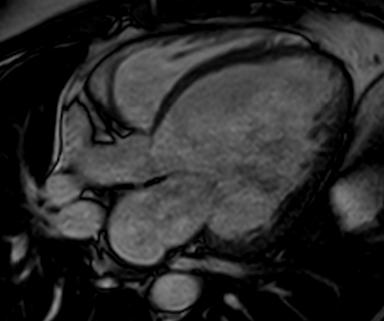

Takotsubo cardiomyopathy is an acute, reversible cardiac syndrome often triggered by emotional or physical stress. It is more prevalent in women and is characterized by transient left ventricular dysfunction, typically involving the apex (apical ballooning).

Imaging: Apical akinesis with preserved basal contraction

Imaging | Dilated chambers, thin walls | Apical akinesis, ballooning |